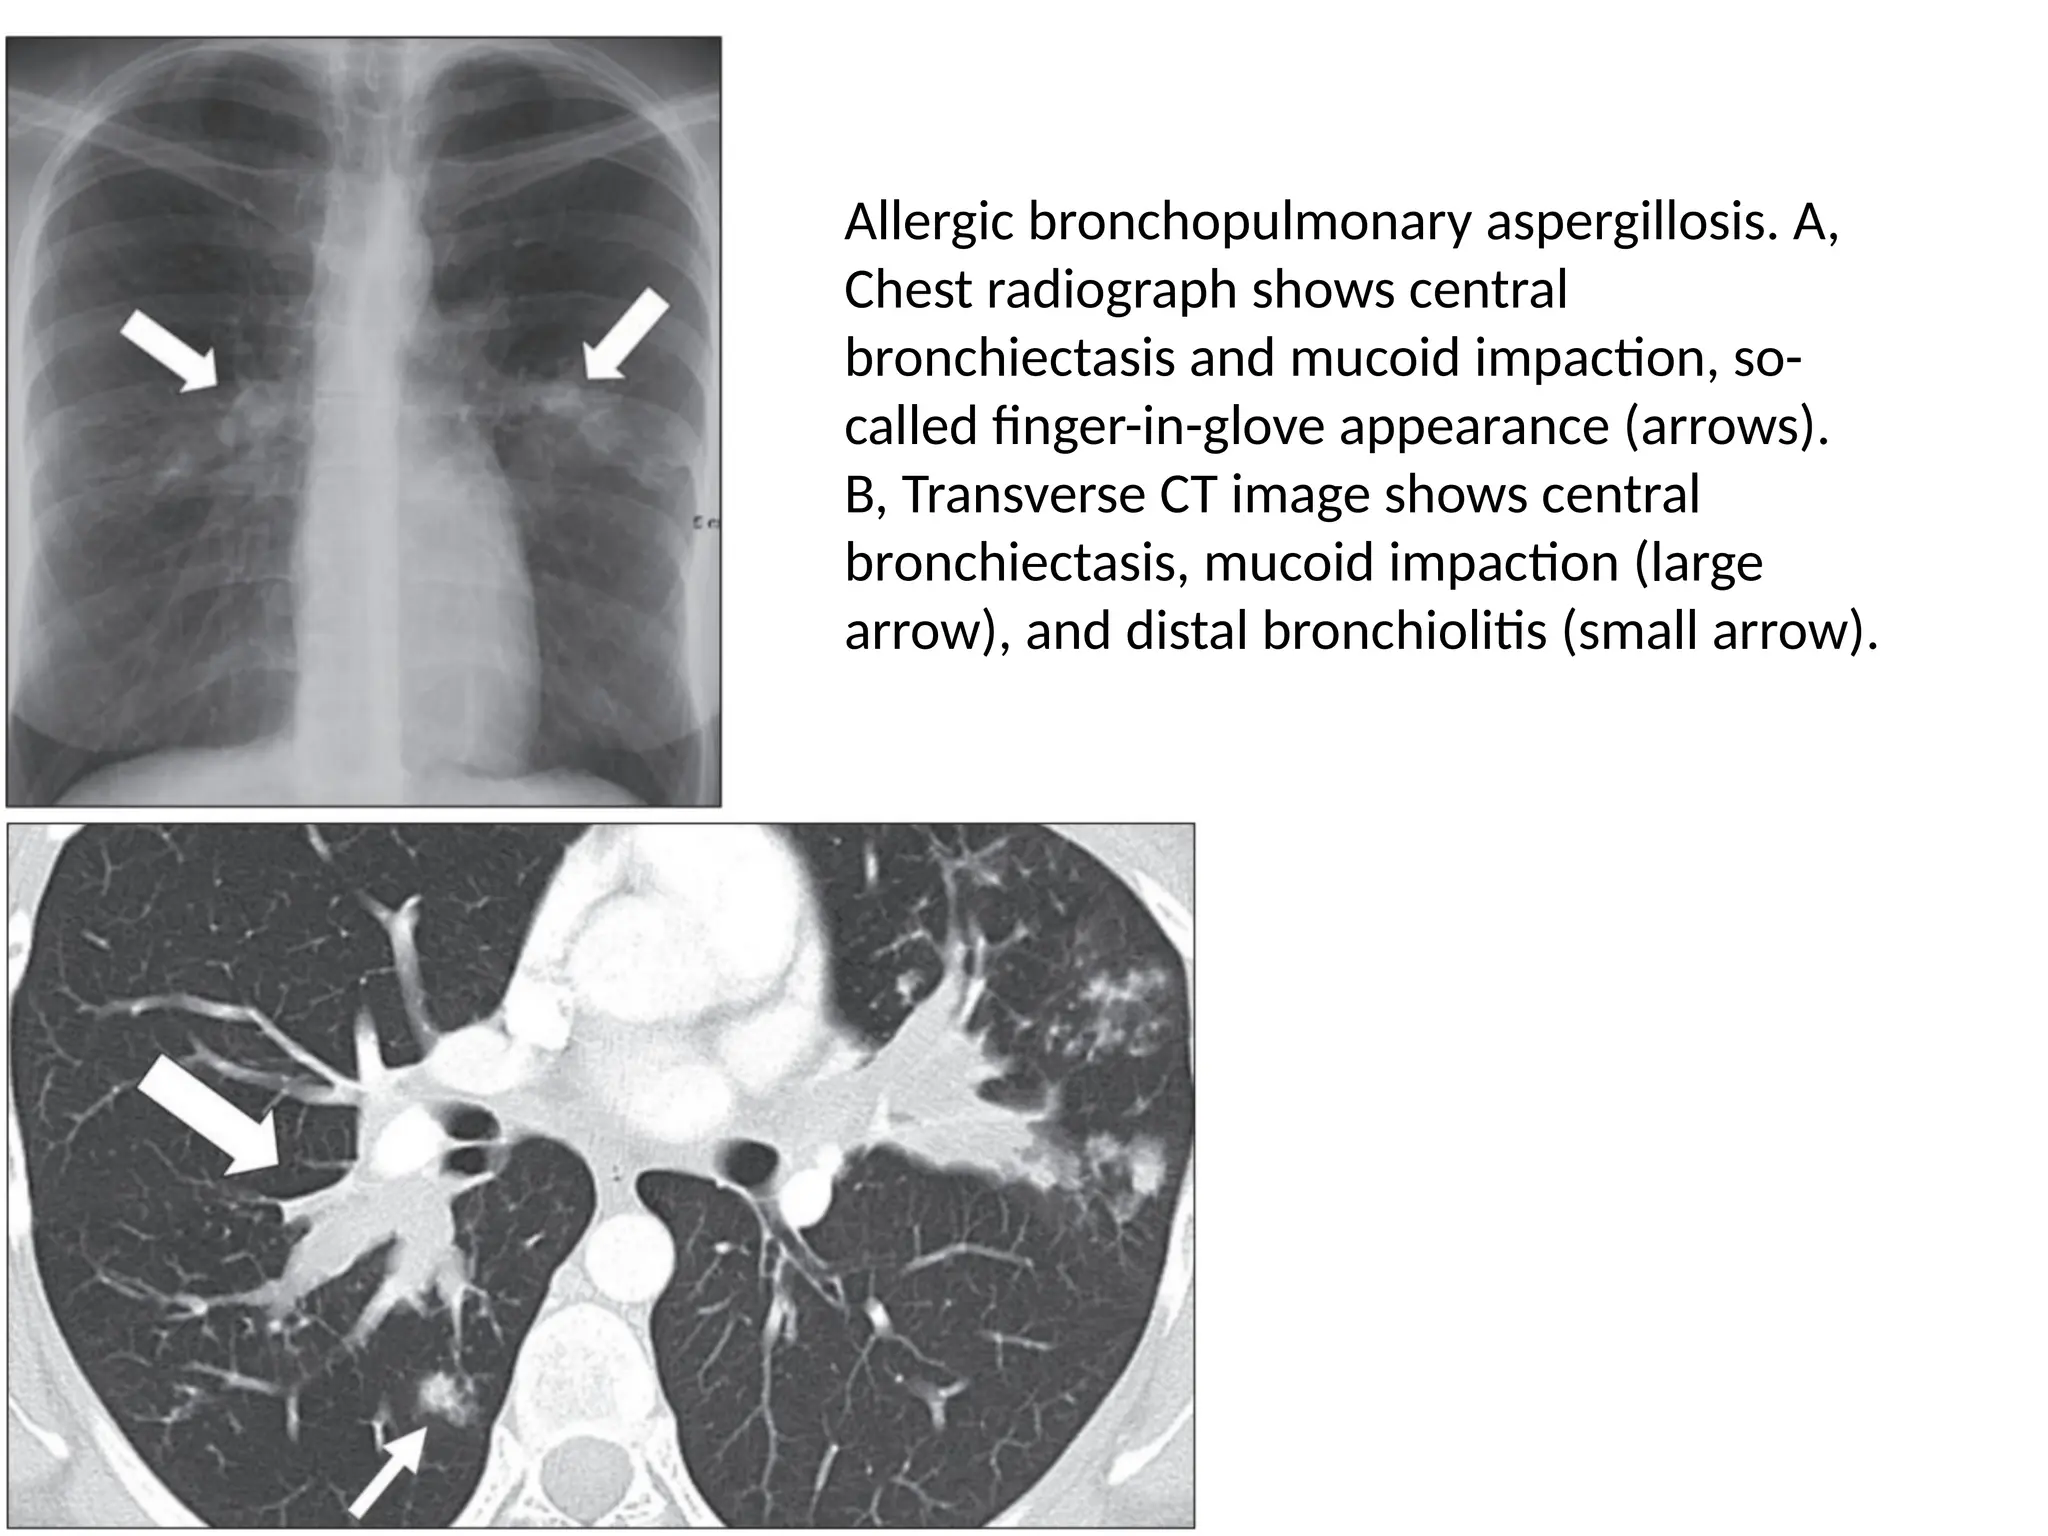

Allergic bronchopulmonary aspergillosis. A,

Chest radiograph shows central

bronchiectasis and mucoid impaction, so-

called finger-in-glove appearance (arrows).

B, Transverse CT image shows central

bronchiectasis, mucoid impaction (large

arrow), and distal bronchiolitis (small arrow).

Allergic bronchopulmonary aspergillosis.A, Chest radiograph shows central bronchiectasis and mucoid impaction, so- called finger-in-glove appearance (arrows). B, Transverse CT image shows central bronchiectasis, mucoid impaction (large arrow), and distal bronchiolitis (small arrow).